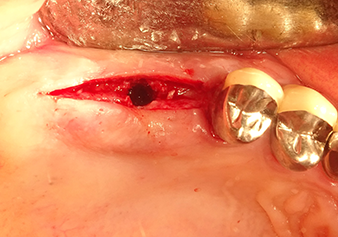

Preoperative findings: The alveolar ridge has healed well, including sufficiently broad, keratinised gingiva

Fig.1: Preoperative findings: The alveolar ridge has healed well, including sufficiently broad, keratinised gingiva.